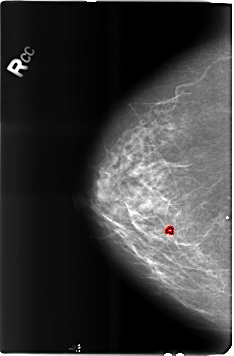

FILE: B_3182_1.RIGHT_CC.OVERLAY

TOTAL_ABNORMALITIES 1

ABNORMALITY 1

LESION_TYPE CALCIFICATION TYPE COARSE DISTRIBUTION N/A

ASSESSMENT 2

SUBTLETY 3

PATHOLOGY BENIGN_WITHOUT_CALLBACK

TOTAL_OUTLINES 1

BOUNDARY